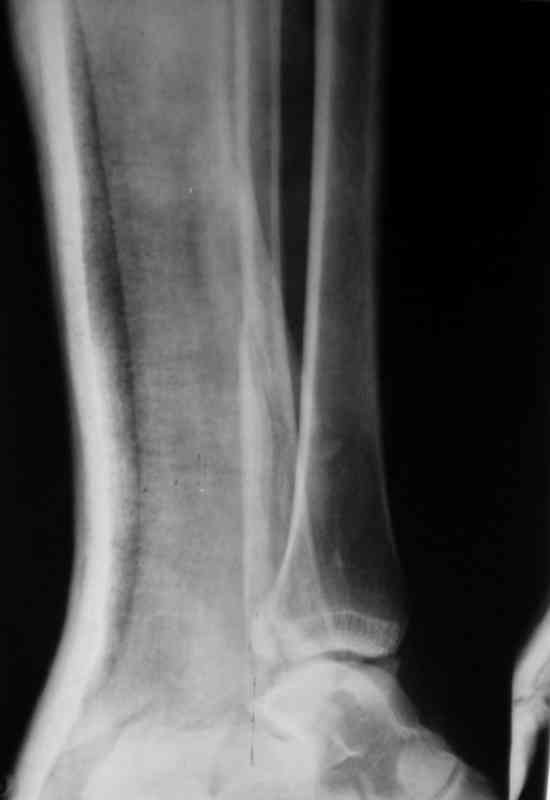

Вот рентгенконтроль на 7-е сутки после репозиции.

Стандартными снимками считается прямая, боковая и мортиз!!!, а так трудно гадать, насколько потеря длины малоберцовой. На боковом снимке не сопоставленный перелом медиальной лодыжки и перелом заднего края без смещения.

Трехлодыжечные переломы относятся к нестабильным переломам, при вовлечении перелома заднего края больше 15% суставной поверхности и смещения более 2 мм тогда такие переломы необходимо оперировать.

Трудно удержать трехлодыжечные переломы задней лонгетной повязкой (на снимке), а последующие долгие гипсовые повязки могут привести к контрактурам.